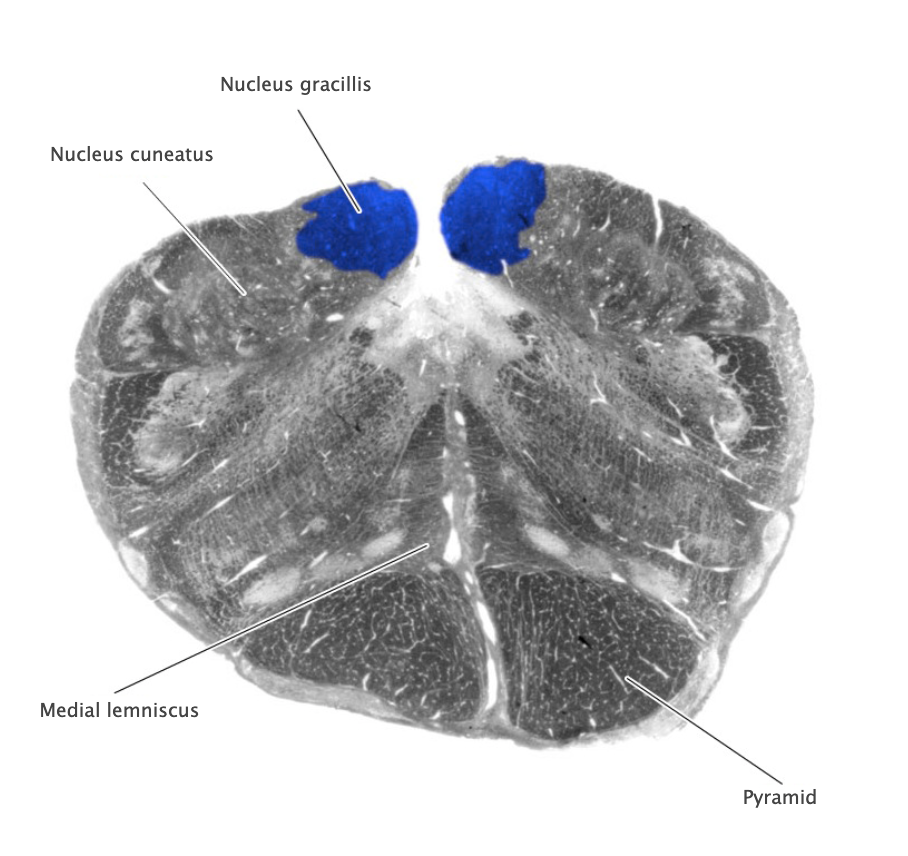

Dorsal column nuclei

Gracile nucleus and cuneate nucleus; contain the second-order sensory neurons that relay mechanosensory information from peripheral receptors in the body (excluding the face) to the thalamus via the medial lemniscus. The dorsal column nuclei are located in the lower medulla.

Nucleus cuneatus

Dorsal column nucleus in the lower medulla; contains second-order sensory neurons that relay mechanosensory information from peripheral receptors in the upper extremities to the thalamus via the medial lemniscus.

Nucleus gracilis

Nucleus containing the second-order sensory neurons that relay mechanosensory information from peripheral receptors in the lower body to the thalamus via the medial lemniscus, located in the lower medulla (also called the "gracile nucleus"). The nucleus gracilis also relays visceral pain information from second-order neurons in the central spinal cord to the thalamus.